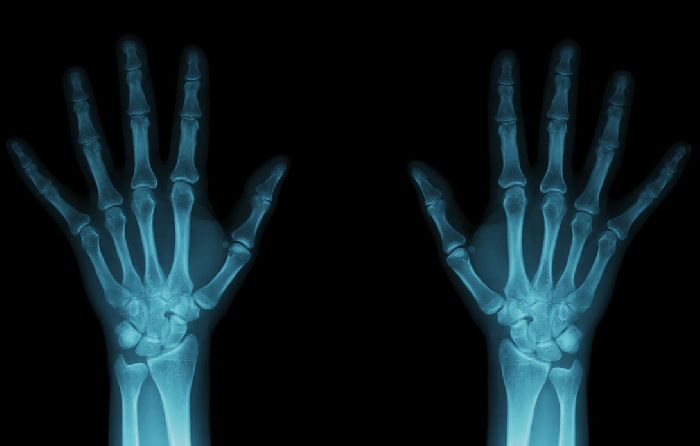

Возможность получения рентгеновских снимков обусловлена тем, что различные ткани по-разному поглощают рентгеновские лучи. Там, где лучи, пройдя через биологическую ткань, не ослабли – воздействие на чувствительный слой экрана будет сильнее, чем там, где лучи были сильно поглощены.

Рис. 1. Примеры рентгеновских снимков.